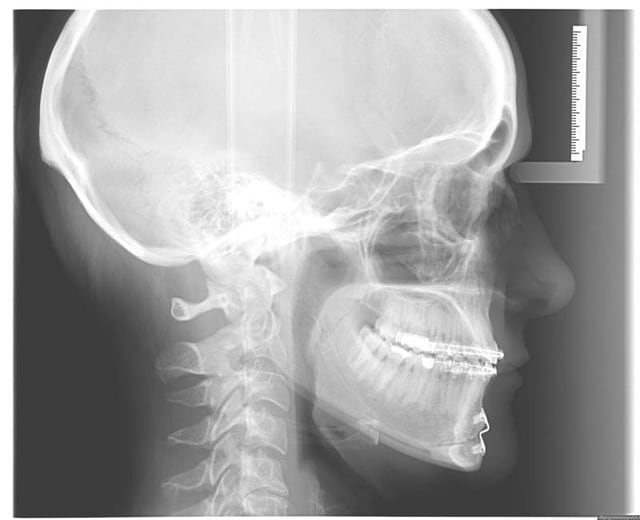

traité en technique de Burstone, puis en friction faible

Il s’agit d’un cas en transfert, qui n’est pas satisfaite du résultat de son traitement O.D.F. (Burstone)

Elle a consulté un chirurgien maxillo qui lui propose un chirurgie haut et bas, et lui a dit qu’elle aurait besoin d’une finition O.D.F.

Comme elle me parle d’extractions des PM. Inf., je lui demande les coordonnées de son chirurgien, et lui demande s’il ne préfère pas que je réaligne les Inc. Inf. avant la chirurgie, quitte à la mettre provisoirement en inversé d’articulé Ant.

Il et elle me donnent leur accord, voici les photos de départ

chronologiquement : elle a subi une chir du menton il y a 3 ans, puis insatisfaite du résultat, un traitement O.D.F. de 2 ans, tjs. insatisfaite , elle est allée consulter un 2° chirurgien, c’est alors qu’elle est venue me voir. Les 1° photos datent de cette époque